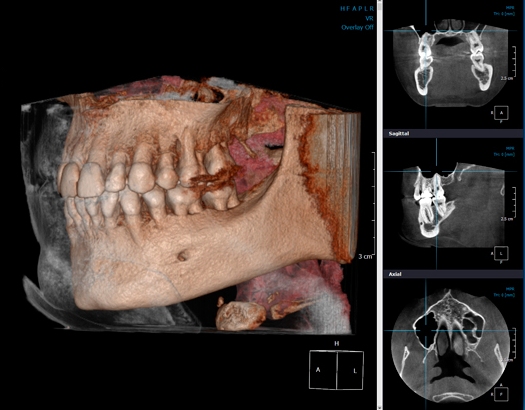

Radiologia digitale CBCT Cranex3D

Metodologie diagnostiche e terapeutiche

- Diagnosi e cura delle disfunzioni mandibolari, cervicali e articolari conseguenti a malocclusione dentale. - Tecniche neuromuscolari di recupero dell'occlusione dentale fisiologica. - Fisioterapia temporo Mandibolare.